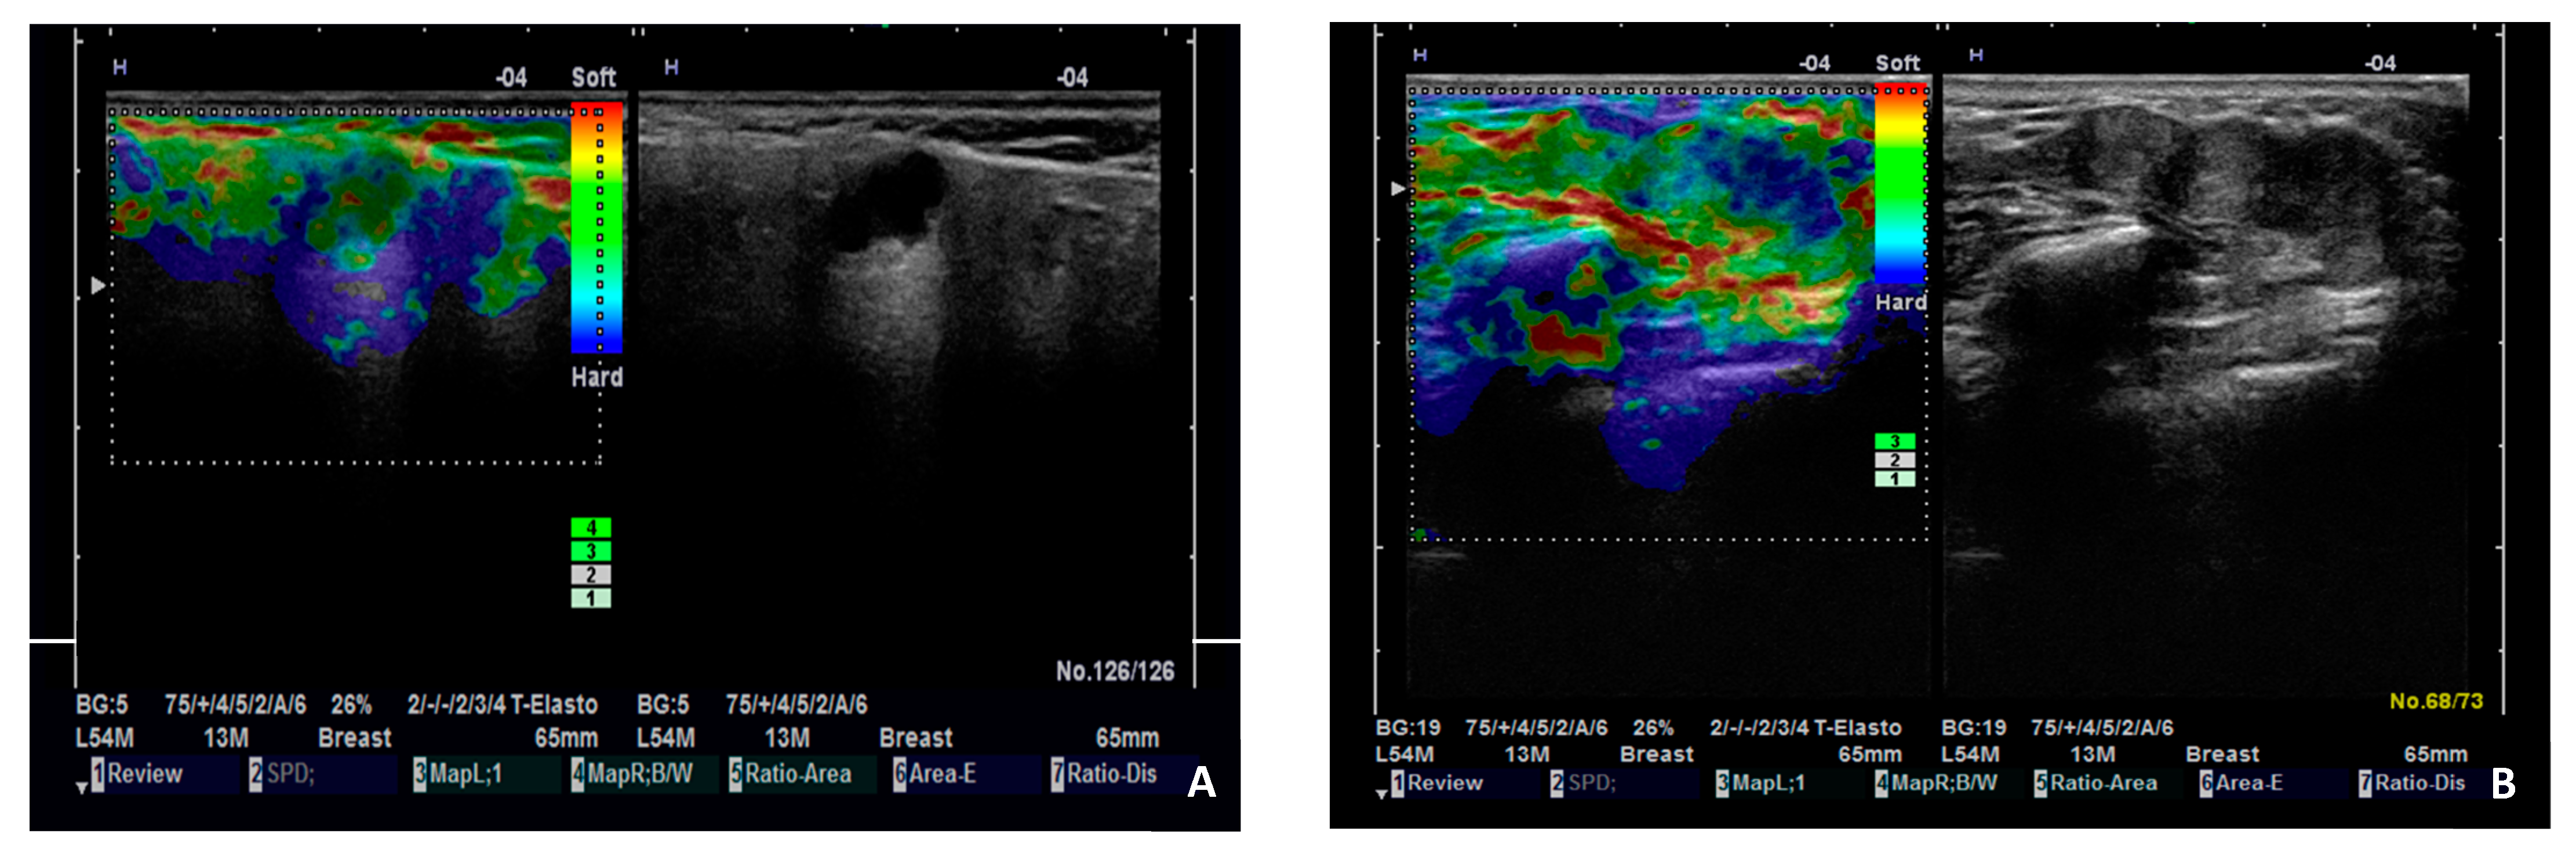

There are contradictory results in studies that assess the diagnostic performance of SE in salivary gland tumors. A four-pattern scoring system to assess salivary gland tumors was proposed: tumors that are completely green, mostly green with some blue areas, mostly blue with some green areas, and entirely blue, corresponding to scores of 1, 2, 3, and 4, respectively. At a cut-off score ≥3, malignancy was detected with sensitivity, specificity, and accuracy of 54.5%, 56.4%, and 56.2%, respectively, by conventional SE, and 77.3%, 63.8%, and 65.4%, respectively, by ARFI-SE. Different SE patterns are presented in Figure 4. The stiffness of malignant tumors located in the deep parotid lobe was hard to assess with ARFI-SE, due to the attenuation of the acoustic push pulses [35].

Figure 4.

Illustration of SE patterns in parotid gland tumors. (A). Pleomorphic adenoma with SE score 1 (almost completely green). (B). Adenoid cystic carcinoma with SE score 3 (mostly blue with some green areas).